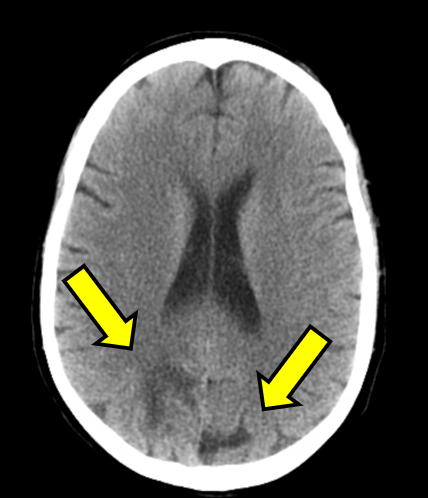

At this point, further workup was initiated: complete metabolic panel, magnesium, phosphorous, thyroid stimulating hormone (TSH) level, ethanol, urinalysis (UA), and urine drug screen (UDS) were obtained, which were notable for improved creatinine of 1.0, calcium of 7.8, mildly decreased TSH of 0.384, nitrite positive UA, and UDS positive for barbiturates, benzodiazepines, and opiates. Non-contrast head CT demonstrated bilateral vasogenic edema in the posterior parietal lobes read as concerning for posterior reversible encephalopathy syndrome (PRES; see Figure 1A). The patient was admitted after consultation with neurology for observation and an MRI.

Figure 1: Computed Tomography and Magnetic Resonance Imaging Demonstrating Posterior Reversible Encephalopathy Syndrome (PRES) Figure Caption: Initial (A) and next-day (B) CT imaging of concerning for PRES, with bilateral parietal vasogenic edema noted. MRI demonstrated expansile T2/FLAIR hyperintense signal in the posterior frontal and parietal lobes, favored to be PRES (C and D). Arrows correspond to areas of interest.

Initial (A) and next-day (B) CT imaging of concerning for PRES, with bilateral parietal vasogenic edema noted. MRI demonstrated expansile T2/FLAIR hyperintense signal in the posterior frontal and parietal lobes, favored to be PRES (C and D). Arrows correspond to areas of interest.